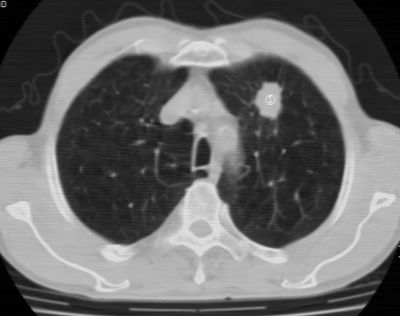

标题: CT24783:m71,既往肺心病史3年,现咳嗽,憋喘。 [打印本页]

标题: CT24783:m71,既往肺心病史3年,现咳嗽,憋喘。

1、左肺上叶spn,毛刺+分叶+血管集束征,考虑周围型肺癌可能性大

2、全小叶性肺气肿。

1)左肺上叶周围型肺癌可能。2)两肺全小叶型肺气肿。

左上周围型肺癌,全小叶型肺气肿。